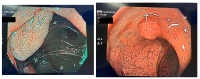

Artificial intelligence (AI) is a term that covers a multitude of techniques that are used in a manner that tries to reproduce human intelligence. AI is helpful in various medical specialties that use imaging for diagnostic purposes, and gastroenterology is no exception. In this field, AI has several applications, such as detecting and classifying polyps, detecting the malignancy in polyps, diagnosing Helicobacter pylori infection, gastritis, inflammatory bowel disease, gastric cancer, esophageal neoplasia, and pancreatic and hepatic lesions. The aim of this mini-review is to analyze the currently available studies regarding AI in the field of gastroenterology and hepatology and to discuss its main applications as well as its main limitations.